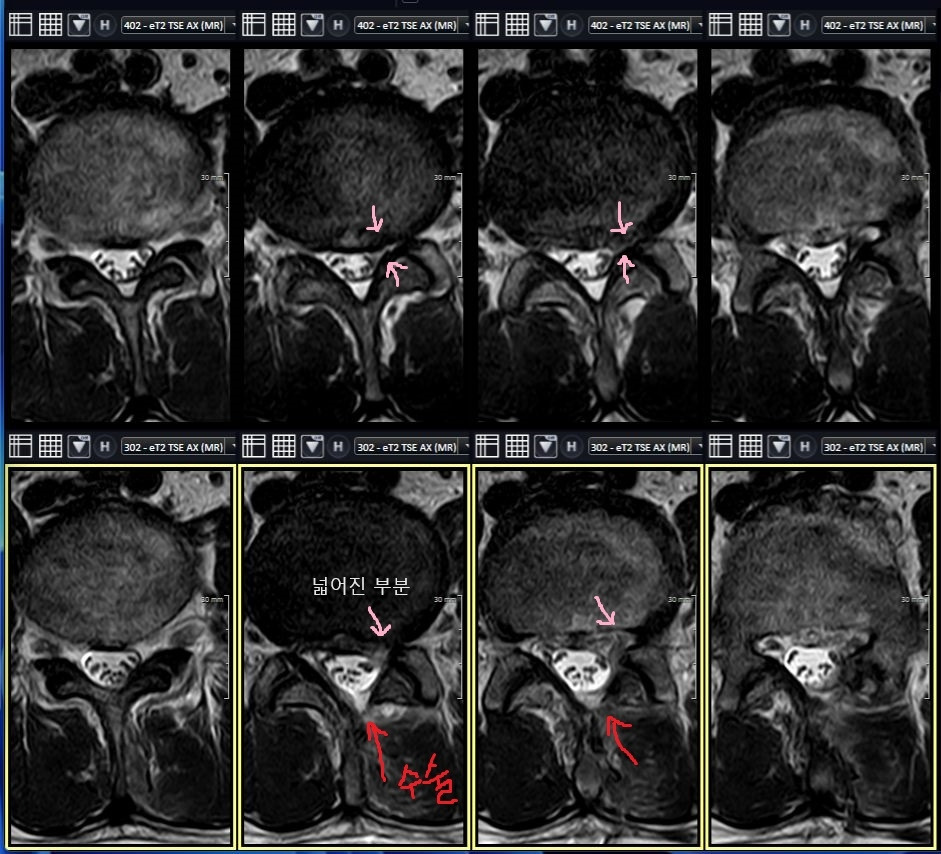

이 분은 증상과 영상 소견이 심하지는 않아보여서 척추신경성형술 했는데 얼마뒤 걷지도 못할 정도로 아파지셨고, f/u MRI상 재파열인듯해 UBE양방향내시경으로 후궁감압술 수술 시행했습니다. 수술 하고나서 하지 방사통은 완전히 사라지셨고 3일만에 퇴원하셨습니다.

다른 척추외과의 선배들과 마찬가지로, Facet(후관절) 손상 최대한 안 주려고 신경써서 했는데, 30도 내시경으로 해서 그런지 손상을 거의 주지 않고 거의 완전하게 보존했고, 보존된 관절은 수술 후 MRI 영상에도 아주 잘 관찰됩니다.(위 4장이 수술전, 아래 4장이 수술후) 후관절 손상 안 주려고 반대편에서 접근하는 방식으로 해볼까 고민도 했었는데 동측 접근으로도 거의 보존되어서 만족스럽습니다.